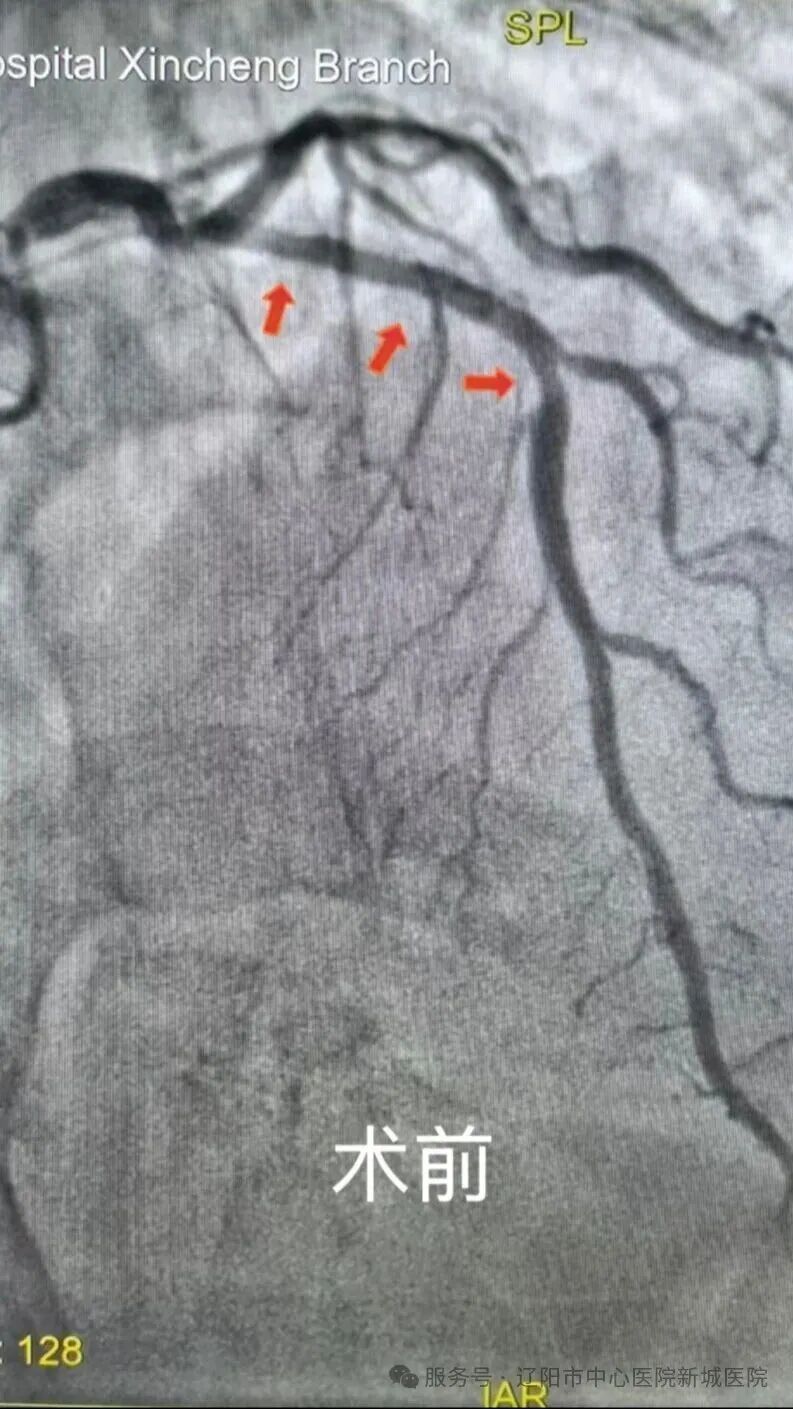

术中,通过血管内超声精准确定病变性质:王女士的左主干开口30%狭窄,回旋支近段20%狭窄,前降支近中段钙化病变最重部位达180°,右冠脉中段50-60%狭窄,病情十分复杂。

在血管内超声的精准引导下,丛主任带领团队先后使用切割球囊、高压球囊对前降支近中段钙化病变进行充分预处理,随后精准植入了药物洗脱支架,手术过程顺利。